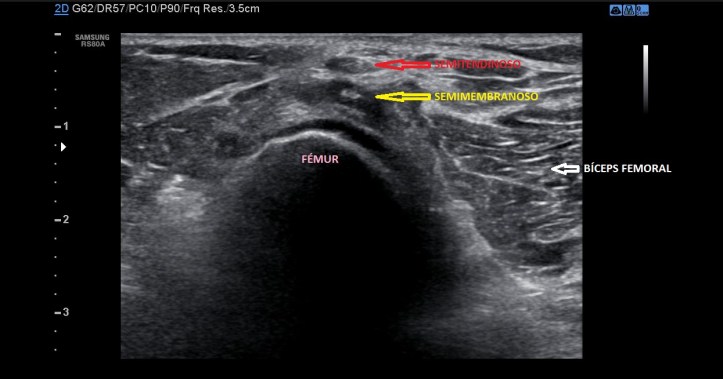

Estos músculos pueden seguirse ecográficamente desde proximal a distal y de interno en la parte proximal, a externo el Bíceps Femoral e interno, el Semimembranoso y el Semitendinoso, que antes de buscar su inserción y en el tercio distal del fémur, se posicionan uno sobre otro…así…Este corte es muy distal y transverso:

La inserción del Bíceps Femoral es diferente, lo hace, tanto su porción larga, como su porción corta, unidas, en la cabeza del Peroné, por tanto lateral. Mira: